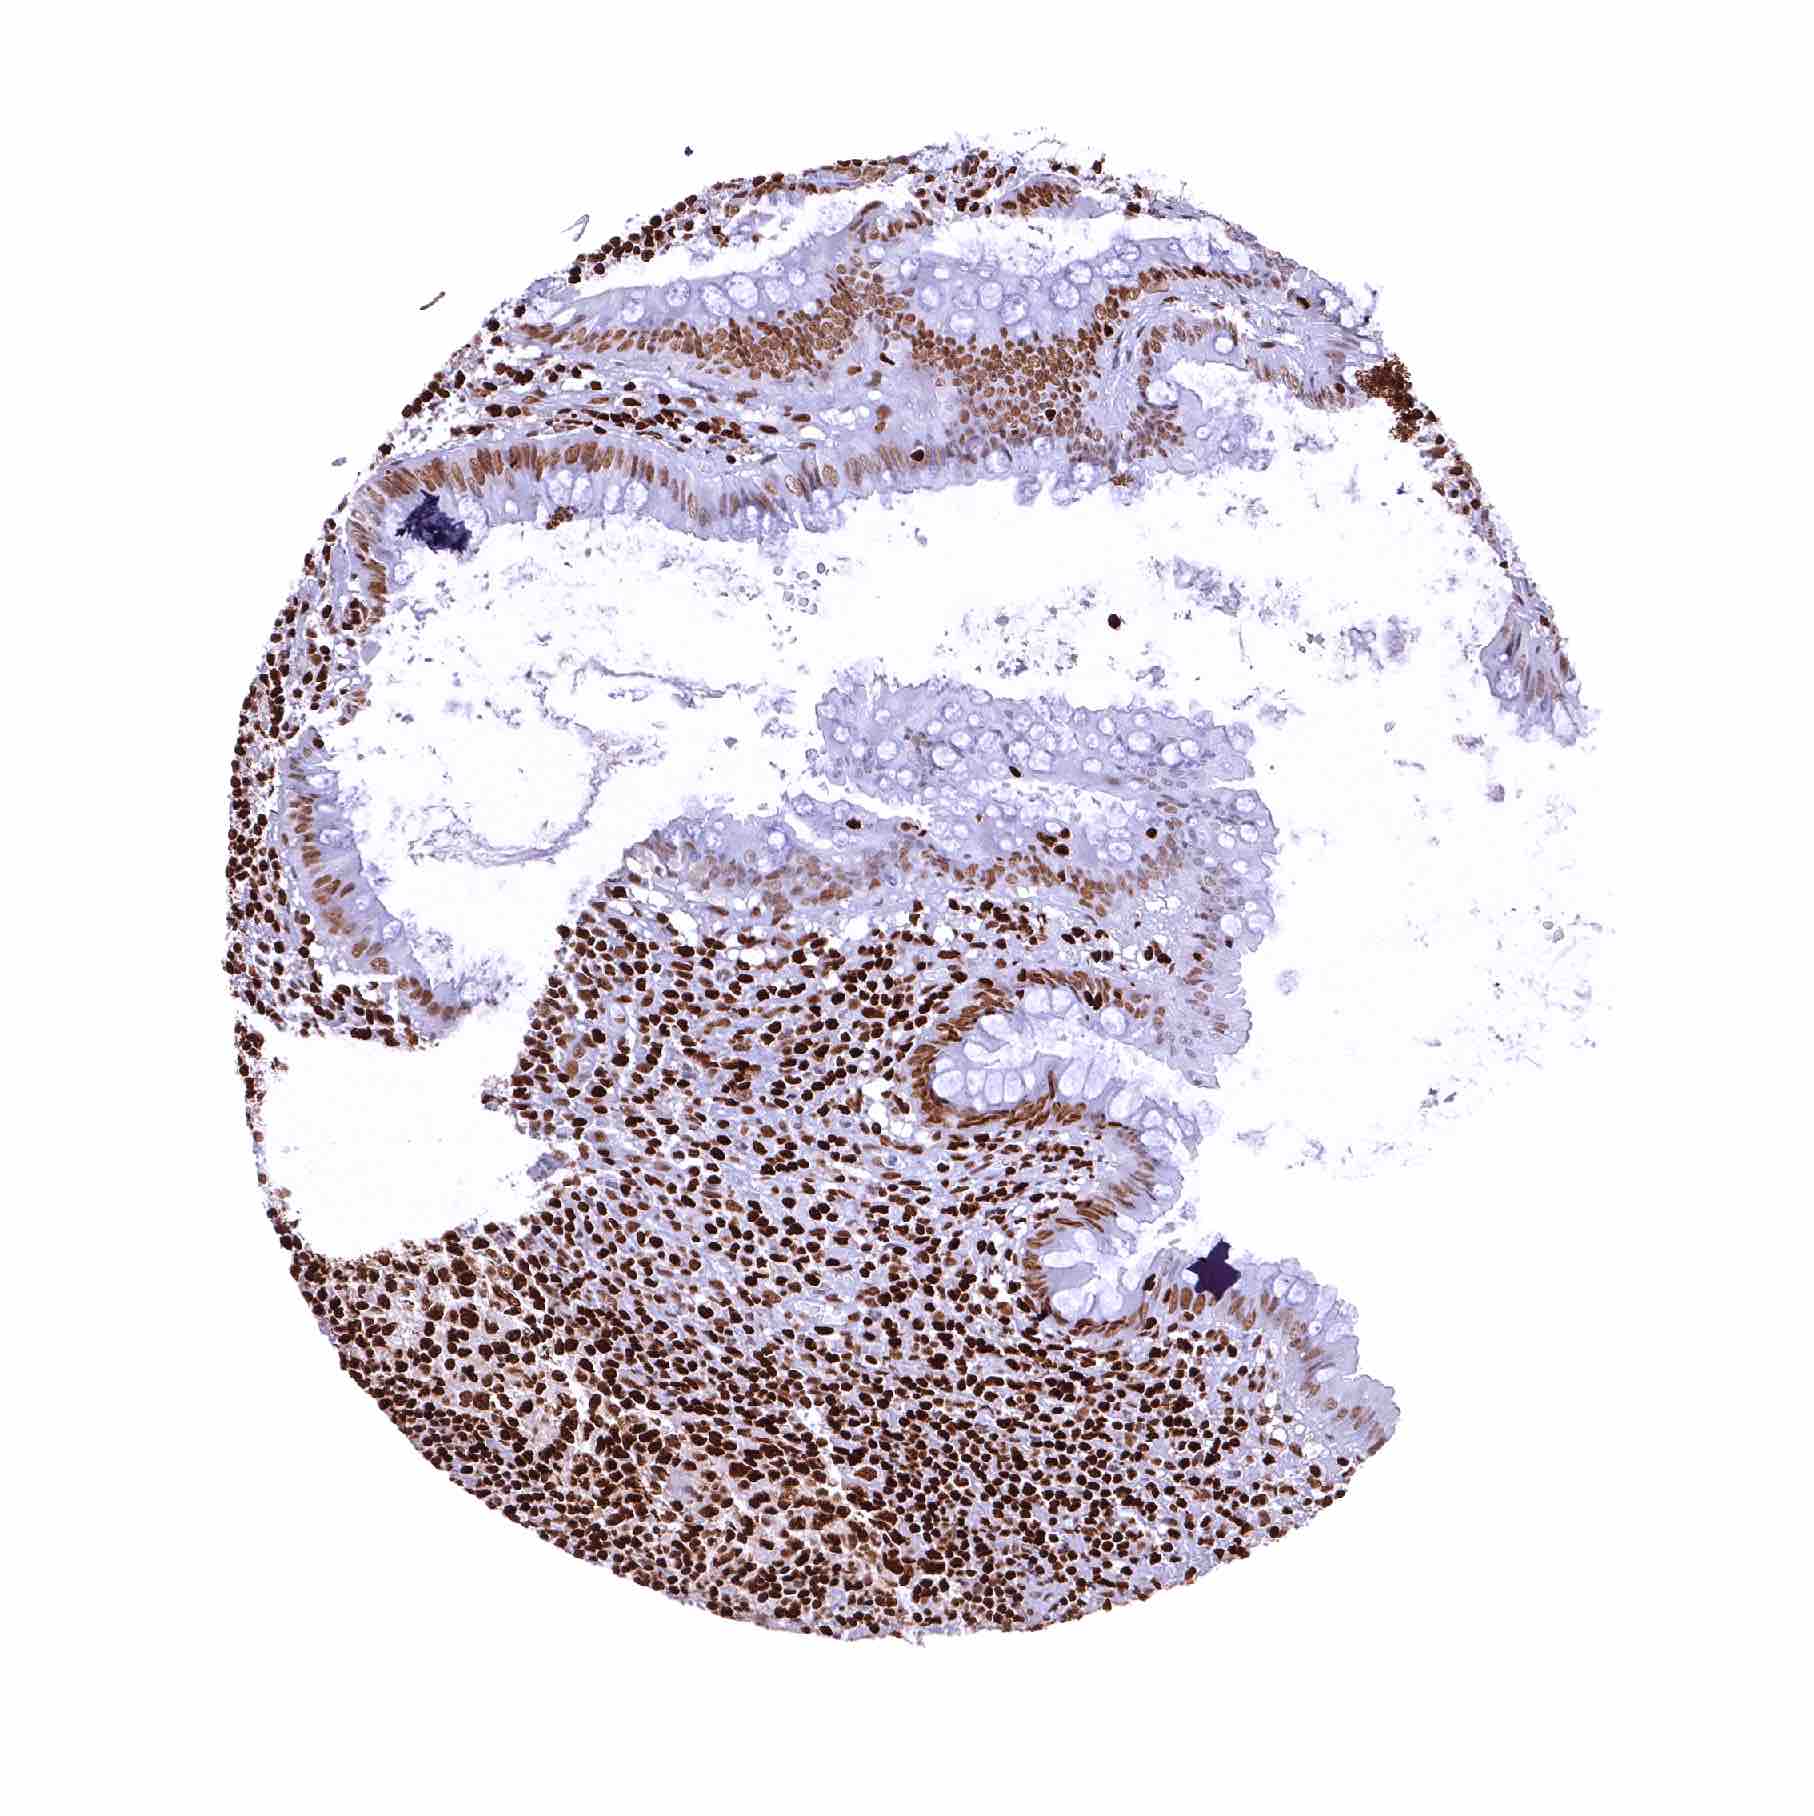

Lymph node